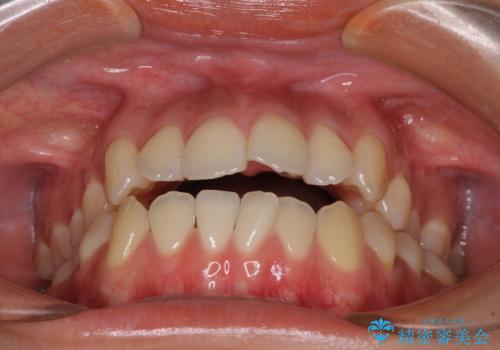

受け口と開咬を急速拡大装置とワイヤー装置で改善

- 前歯の開咬と、受け口による咬み合わせの悪さを気にして来院された患者様です。

上顎歯列が狭窄していたため、急速拡大装置により上顎骨を側方に拡大し、その後ワイヤー装置にて矯正治療を行うこととしました。